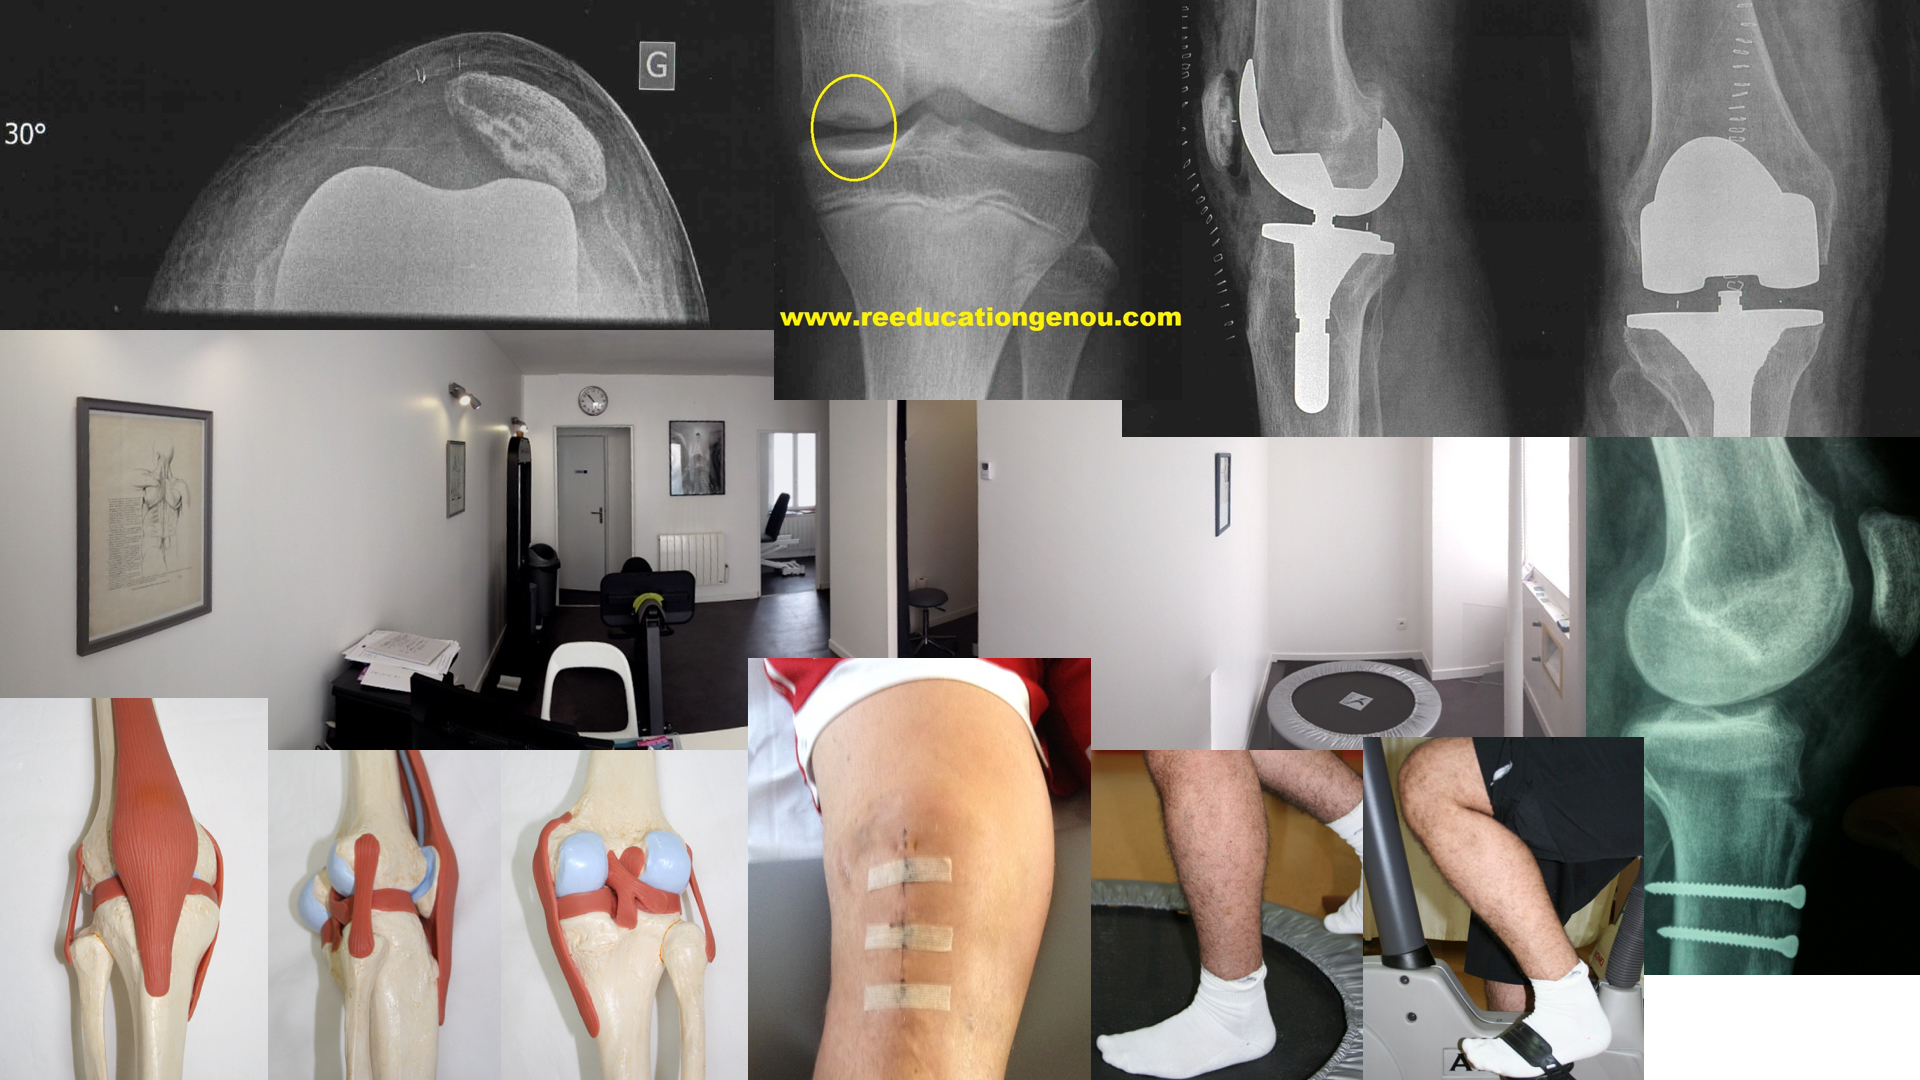

Genou Gauche avec les ancres de suture du LLI

Dr Jacques Tremoulet, cliniques des Maussins 75019 Paris

(et plastie du LCA avec un KJ)